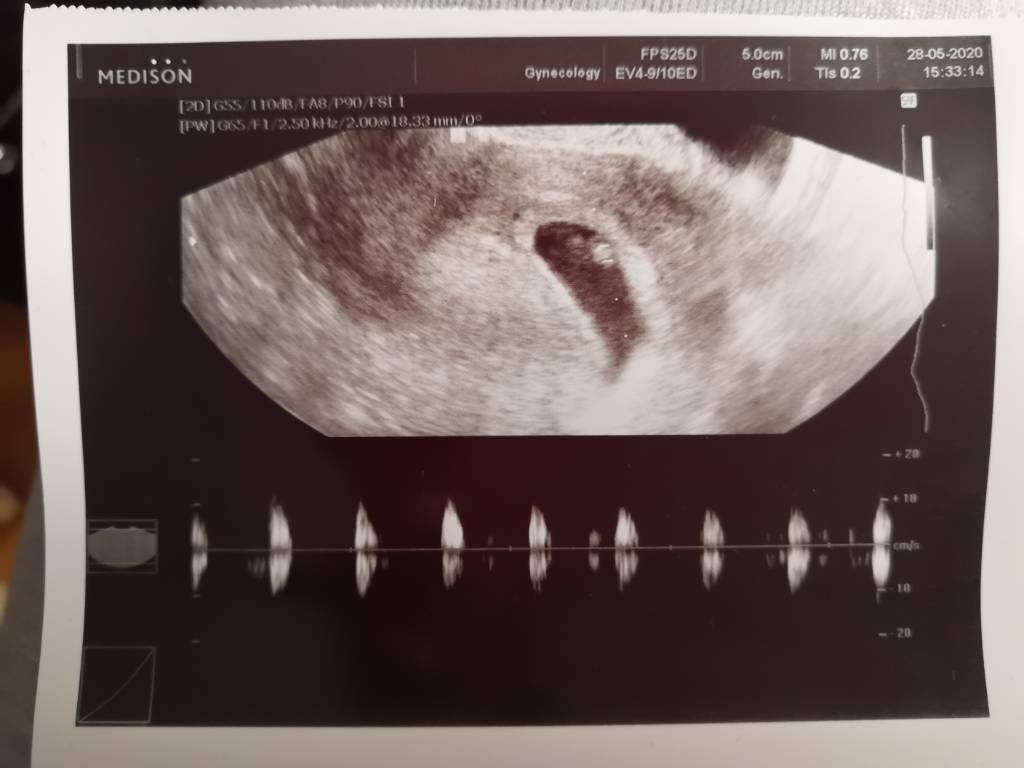

Ja po wizycie już dosyć dawno, wszystko jest dobrze :) maluszek ma 1,64cm to 8tc+0 czyli idzie mi idealnie z miesiączka 😁 akcja serduszka koło 160 :) dodaje też zdjęcia ❤️ ależ jestem szczęśliwa, nie macie pojęcia 🥰 od razu po wizycie położna pobrał mi krew do badań i karta ciąży założona ❤️

No, wiedziałam że dziewczyny pomogą [emoji3059] zerknij jaka u mnie była różnica pomiędzy 6t6d a 8t3d [emoji116]

No, wiedziałam że dziewczyny pomogą [emoji3059] zerknij jaka u mnie była różnica pomiędzy 6t6d a 8t3d [emoji116]Zobacz załącznik 1133982Zobacz załącznik 1133983